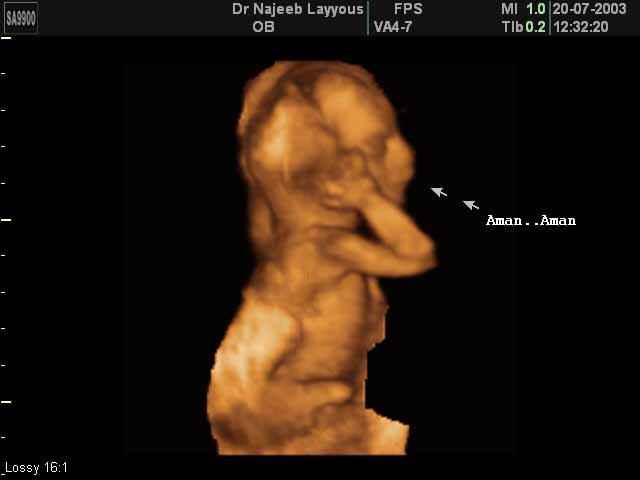

3D second trimestre échographie Photos de numérisation - deuxième partie de la grossesse | Dr N Layyous

3D second trimestre échographie Photos de numérisation - deuxième partie de la grossesse